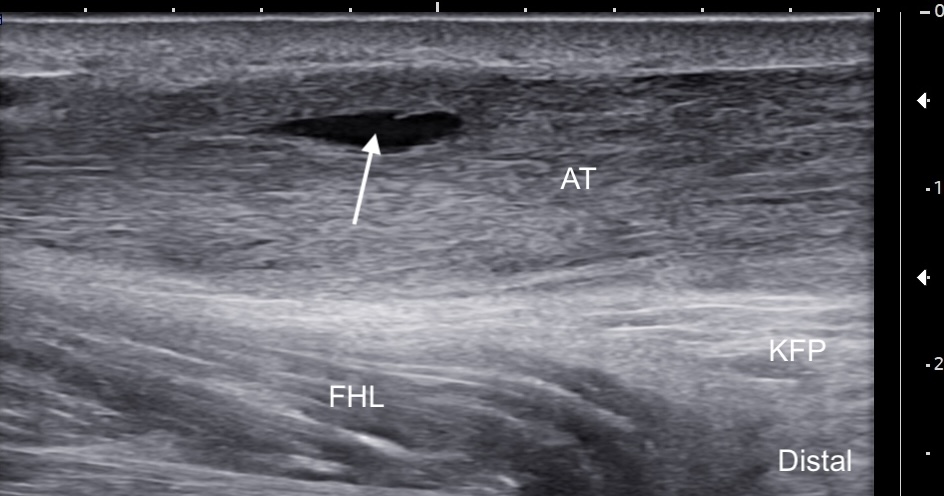

Labeled long-axis ultrasound image of the midportion Achilles tendon showing increased thickness with the tendon exhibiting a convex shape and a longitudinal intrasubstance partial tear. The partial tear (solid arrow) is surrounded by hypoechogenic tendinotic tissue with loss of normal fibrillar architecture, while some healthy-appearing fibers remain, including deep to the tear. Labels: AT: Achilles tendon, FHL: Flexor hallucis longus, KFP: Kager's fat pad, solid arrow: partial tear